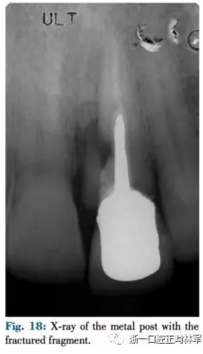

患者為一名57歲高加索人,左上中切牙受傷(圖17,18),近中唇側探診9mm,唇側探診5mm。X片提示根折及骨缺損。由于美學效果差因此不采用冠延長術,此外由于其冠根比較差不采用牽引及修復治療。